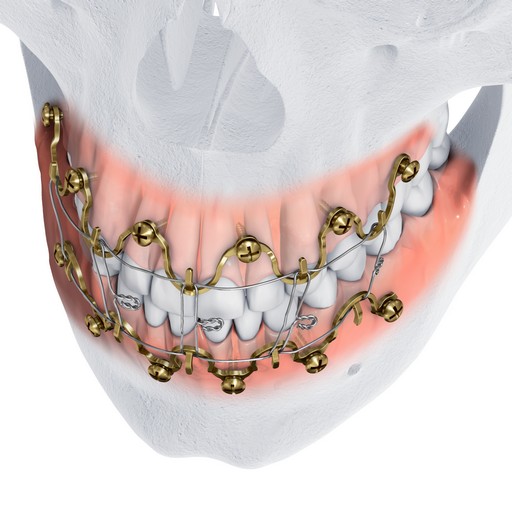

MatrixWAVE MMF (Figs 1-8) is a novel bone-borne MMF system that combines the strength and rigidity of arch bars with the speed and simplicity of IMF screws. It consists of a wave shaped plate that is attached to the mandible and maxilla with self-drilling locking screws (Fig 3). The plate is adaptable and can be extended horizontally (Fig 4) to allow screw hole placement in the optimal location to avoid tooth roots and nerves. The locking mechanism avoids compression and ischemia by keeping the plate away from the mucosal tissues.

The dental arches are brought into occlusion by wiring around the plate hooks and/or accessible screw heads. The self-drilling locking screws sit proud to the plate. This minimizes soft tissue growth over the screw, and provides additional anchor points for optional bridle wires. Upon insertion, screws can be angled at up to 15 to aid in posterior fixation and to optimize dental occlusion.

Following application and wiring, the wave plate pattern allows the alignment of bone segments to be adjusted by crimping without repositioning the screws. The plate is available in two heights to allow the positioning of the hooks at the level of the tooth equators according to individual patient anatomy, and to accommodate the use of rigid internal fixation (Fig 2).

The MatrixWAVE plate was attached to the maxilla with screw placement in the inter-root spaces (Fig 2). A second MatrixWAVE plate was attached in corresponding position to the mandible, with screw placement in the inter-root spaces (Fig 3). Wires were placed around the plate hooks to bring the dental arches into occlusion. Note the preexisting anterior open bite (Fig 4). Careful adjustment of the MatrixWAVE plate and wiring in the region of the mandibular fracture allowed the bone fragments to be precisely aligned without the requirement for screw repositioning (Fig 5). The postoperative panoramic x-ray (Fig 6) shows the two MatrixWAVE plates in situ, with other plates used to fixate the left mandibular angle fracture. Note that a portion of the Matrix- WAVE plate was removed from the left molar region in the mandible (Fig 6).